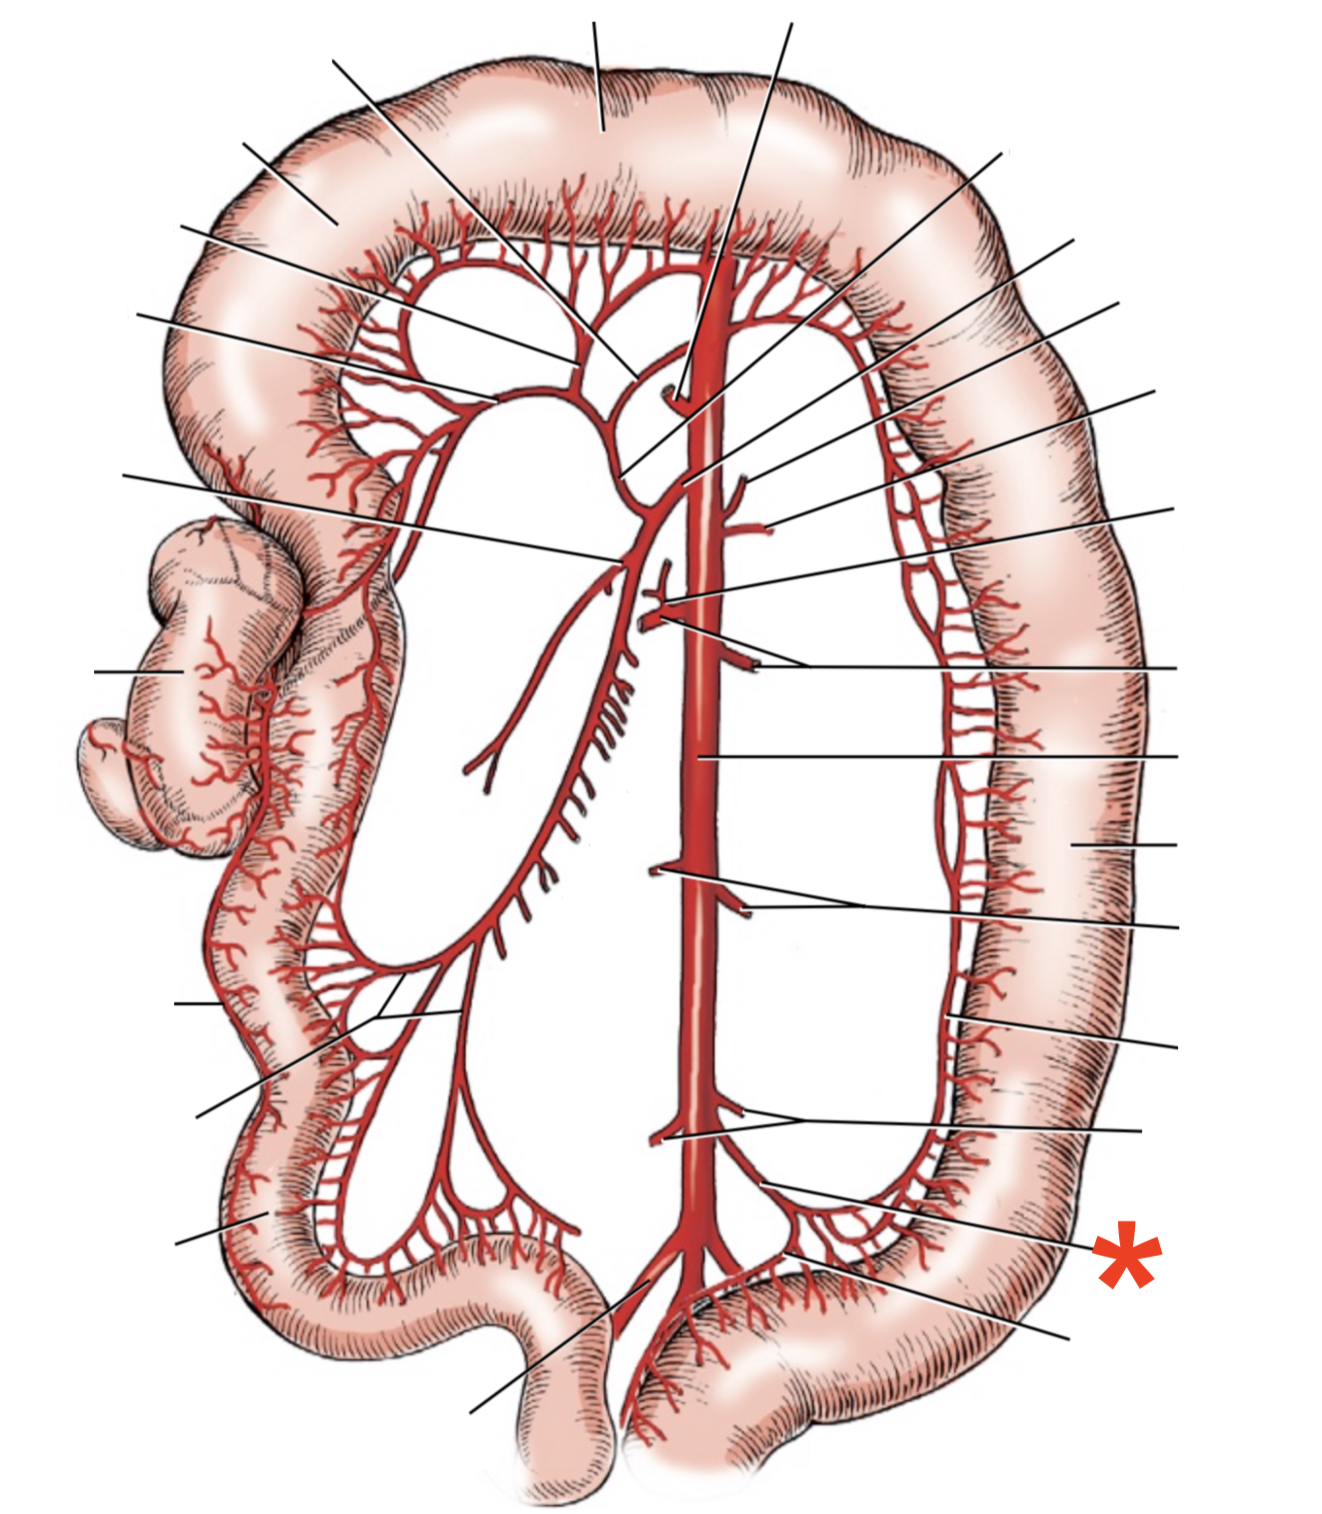

A

A. mesenterica cranialis

15

Q

A

A. pancreaticoduodenalis caudalis

16

Q

A

Aa. jejunales

17

Q

A

A. ilei

- Anastomises with r. ileus mesenterialis a. iliocolica

18

Q

A

A. ileocolica

19

Q

A

A. colica dextra

20

Q

A

A. colica media

21

List the branching of *a.* *mesenterica* *caudalis*

* *A. colica sinistra*

* *A. rectalis cranialis*

List the branches of *a.* *mesenterica* *cranialis*

* *A.* *pancreaticoduodenalis* *caudalis*

* *Aa. jejunalis*

* *A. ilei*

* Common trunk

* A. colica media

* A. colica dextra

* *A. ileocolica*

* *R. ilei mesenterialis*

* *A. cecalis*

* *R. colicus*